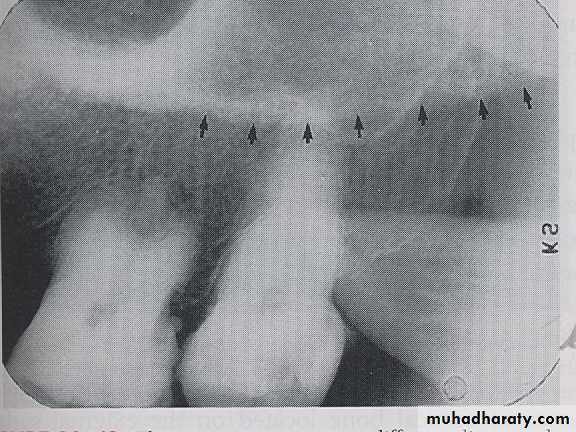

SUB MANDIBULAR FOSSE:

Submandibular fosse is a scooped–out depressed area of bone located on the internal surface of mandible inferior to mylohyoid ridge. On periapical radiography the submandibular fosse appears as radiolucent area in the molars region below the mylohyoid ridge.